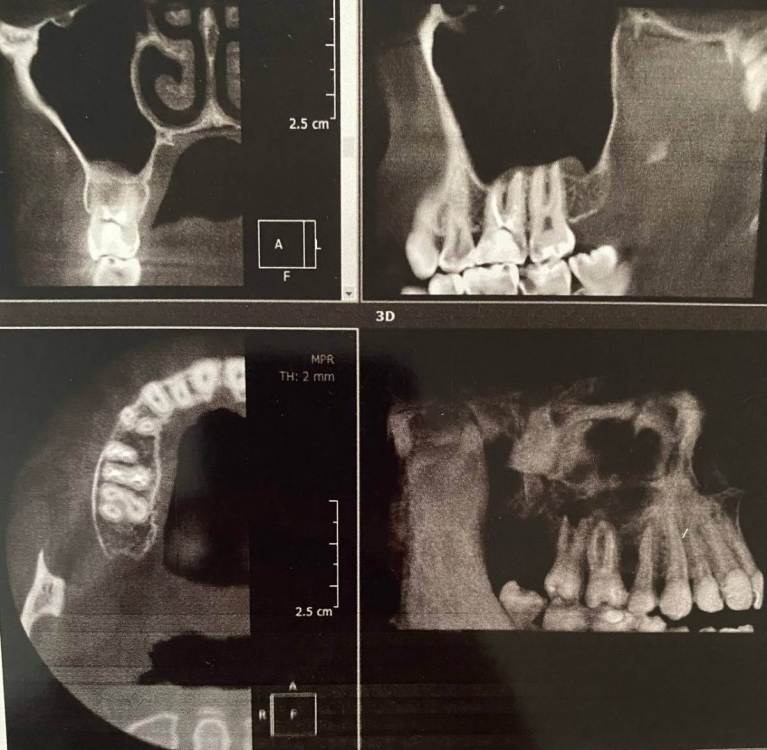

Здравствуйте. В начале марта я сходила на прием, была пролечена (депульпированна) верхняя правая шестерка. После установки временной пломбы в течение двух недель не прекращались ноющие ощущения, поэтому было решено с врачом перелечить зуб. Зуб перелечили, но ноющие боли по-прежнему остались. Зуб не реагирует на холодное/горячее, не шатается, однако реагирует на постукивания.

Была у лора, в одной пазухе есть полип. Может ли он влиять на зуб? Также была у окулиста и невролога с целью исключения патологии тройничного нерва. С этим все в порядке.

Два дня назад треснула эмаль зуба и врач хочет поставить все-таки временную коронку. Я пока сомневаюсь и честно говоря не знаю, что делать, потому что эти странные ноющие ощущения в зубе по-прежнему актуальны. Да и как ставить коронку на зуб, который болит от того, что по нему стучат?...

Была уже у трех врачей, но все говорят, что зуб запломбирован нормально и четкого ответа никто дать не может.

Буду благодарна за любую помощь и ответ. photo_2023-08-09_18-14-31.thumb.jpg.e23f86db67c6866262d362dc6a8b8242.jpgphoto_2023-08-09_18-14-29.thumb.jpg.b2e19e72b9027bf4e4a44185f0ca97e4.jpgphoto_2023-08-09_18-14-25.thumb.jpg.afbef81bf80ad897dc7ffd28efc2453a.jpg

photo_2023-08-09_18-14-28.jpg